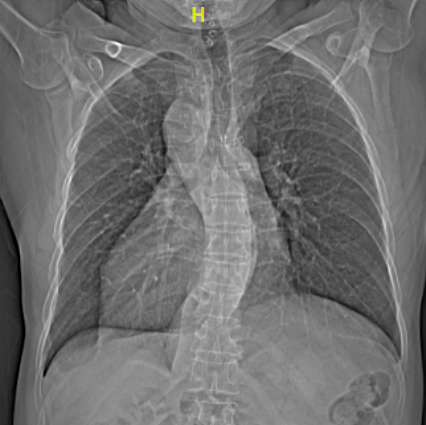

与正常人心脏位置偏左,心尖部在胸腔左侧相反,66岁的梁大叔心脏却长在了右胸腔,好像是正常心脏在镜子里的“影子”,医学上叫做“镜像右位心”。1年前,他一活动就感到心慌气喘,出现反复心悸等症状,被确诊为房颤。

进一步的心脏超声检查发现,梁大叔不仅有右位心,还有永存左上腔的先天性畸形,手术治疗又增加了不少难度。这些先天心脏畸形不仅会造成医生手术操作的不便,而且术中穿刺和导管放置稍有不慎,就可能出现穿孔、大血管损伤、心脏填塞等致命风险。面对如此棘手的手术,不少电生理团队都难以“接招”,梁大叔和家属多方打听,慕名来到主播福利 。

相关数据显示,先天性镜像右位心发病率约十万分之一,而合并房颤介入手术治疗的患者,更是寥寥无几。为此类特殊患者做手术,将极大考验电生理团队的手术操作技巧及逆向思维能力。

不久前引进厦心的亚洲首台心血管专用型CT率先上阵,对患者进行了高精度的心脏扫描,清晰显示了心腔结构、肺静脉及毗邻组织等,为手术开展提供了高质量的影像基础。术中则应用了先进的三维电解剖标测系统,在心腔内超声指导下,常栋、李强两位主任医师率队凭借扎实的手术功底,成功在非常规位置穿刺房间隔,实现了导管精准定位,消融了病灶,更在术中尽可能减少了x线的应用。短短不到三小时,长期困扰梁大叔的房颤终于顺利解除,这颗特殊的心脏也恢复了正常的节奏。